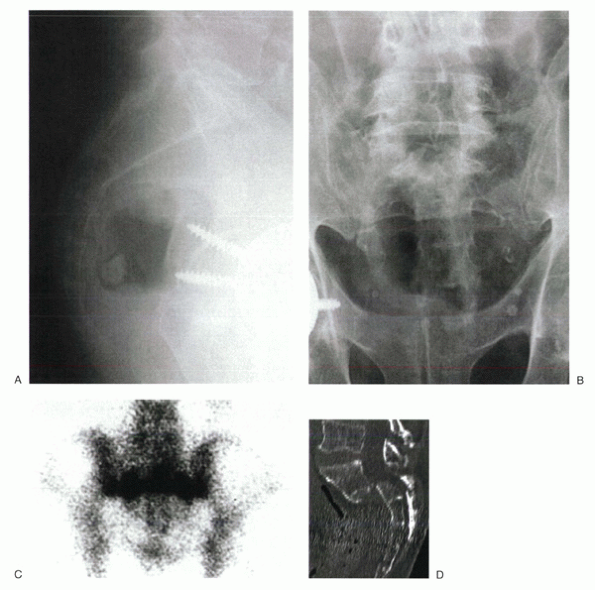

![]() |

Figure 24-2

A 63-year-old woman with postmenopausal osteoporosis was admitted to the hospital with bladder incontinence and severe back pain after a slip and fall injur. MRI showed an L1 osteoporotic burst fracture with conus compression. |

Figure 24-3 Bone scan shows intense uptake at T11 in a patient with 4 months of pain after sustaining a vertebral compression fracture.

compromise. Fracture acuity may be determined by bone scan (Fig. 24-3).

MRI and CT show sacral insufficiency fractures. On bone scan, these

lesions may have the classic H configuration or may appear as a linear

band of increased uptake in the region of the sacral ala (Fig. 24-4C).

Figure 24-4

An 84-year-old man complained of severe sacral pain after “sitting down too hard.” He was point tender over the sacral body, and his pain increased with Patrick’s test. Initial antero-posterior (A) and lateral (B) radiographs show only osteopenia. Scintigraphy in patients with sacral insufficiency fractures generally shows intense uptake, often in an “H” pattern, over the sacrum (C). This patient was mobilized gradually, but sustained a second episode of falling into his hard kitchen chair. New lateral radiographs showed complete displacement of the S1-2 segment. CT scan with sagittal reconstructions shows a transverse fracture through S1-2 (D). MRI typically shows an abnormal signal pattern through the sacral ala (E). After his second fall, the patient reported urinary retention and ultimately was admitted to the hospital for pyelonephritis. He had toe flexor weakness. He underwent a laminectomy and noted improvement in neurologic symptoms (F). |